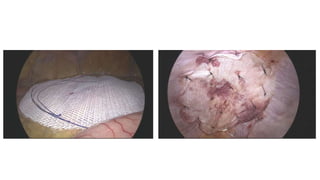

STEP 5: Deploying and Anchoring the Mesh

• A large (15x12 cm) polypropylene mesh.

• The mesh is inserted from the Camera trocar. Then, the mesh is

placed in the appropriate position and fixed by 1 Polypropylene

sutures (or tacking staples, glue in some centres). The first suture is at

the level of pubis

• The mesh is fixed on the upper and internal edge

• The mesh shouldn’t be sutured/stapled at the level of dangerous

triangles and epigastric vessels

The 15X12 cm Mesh is folded & inserted

The Mesh should cover Myopectineal orifice

When the mesh is smoothed out, it overlaps the pubic bone & crosses midline

TIP – wrinkles or folds should not be seen

•The mesh is fixed on the upper and internal edge

3 Point Fixation